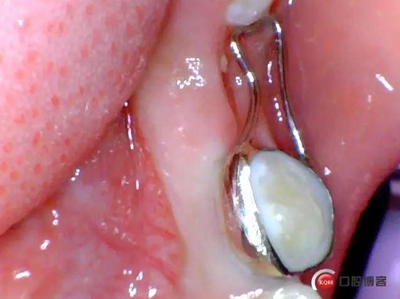

一周后患者復(fù)診,拔牙創(chuàng)恢復(fù)良,制作*74口內(nèi)帶環(huán)并焊接,反復(fù)試戴合適后藻酸鹽取上下頜模型并發(fā)加工廠做保持器。電話預(yù)約復(fù)診時間。

3.jpg

保持器回來后電話預(yù)約患者復(fù)診,反復(fù)試戴合適后消毒隔濕干燥,常規(guī)富士Ⅸ粘結(jié)保持器,調(diào)合,拋光,囑患者注意口腔衛(wèi)生并預(yù)約半年復(fù)查一次。